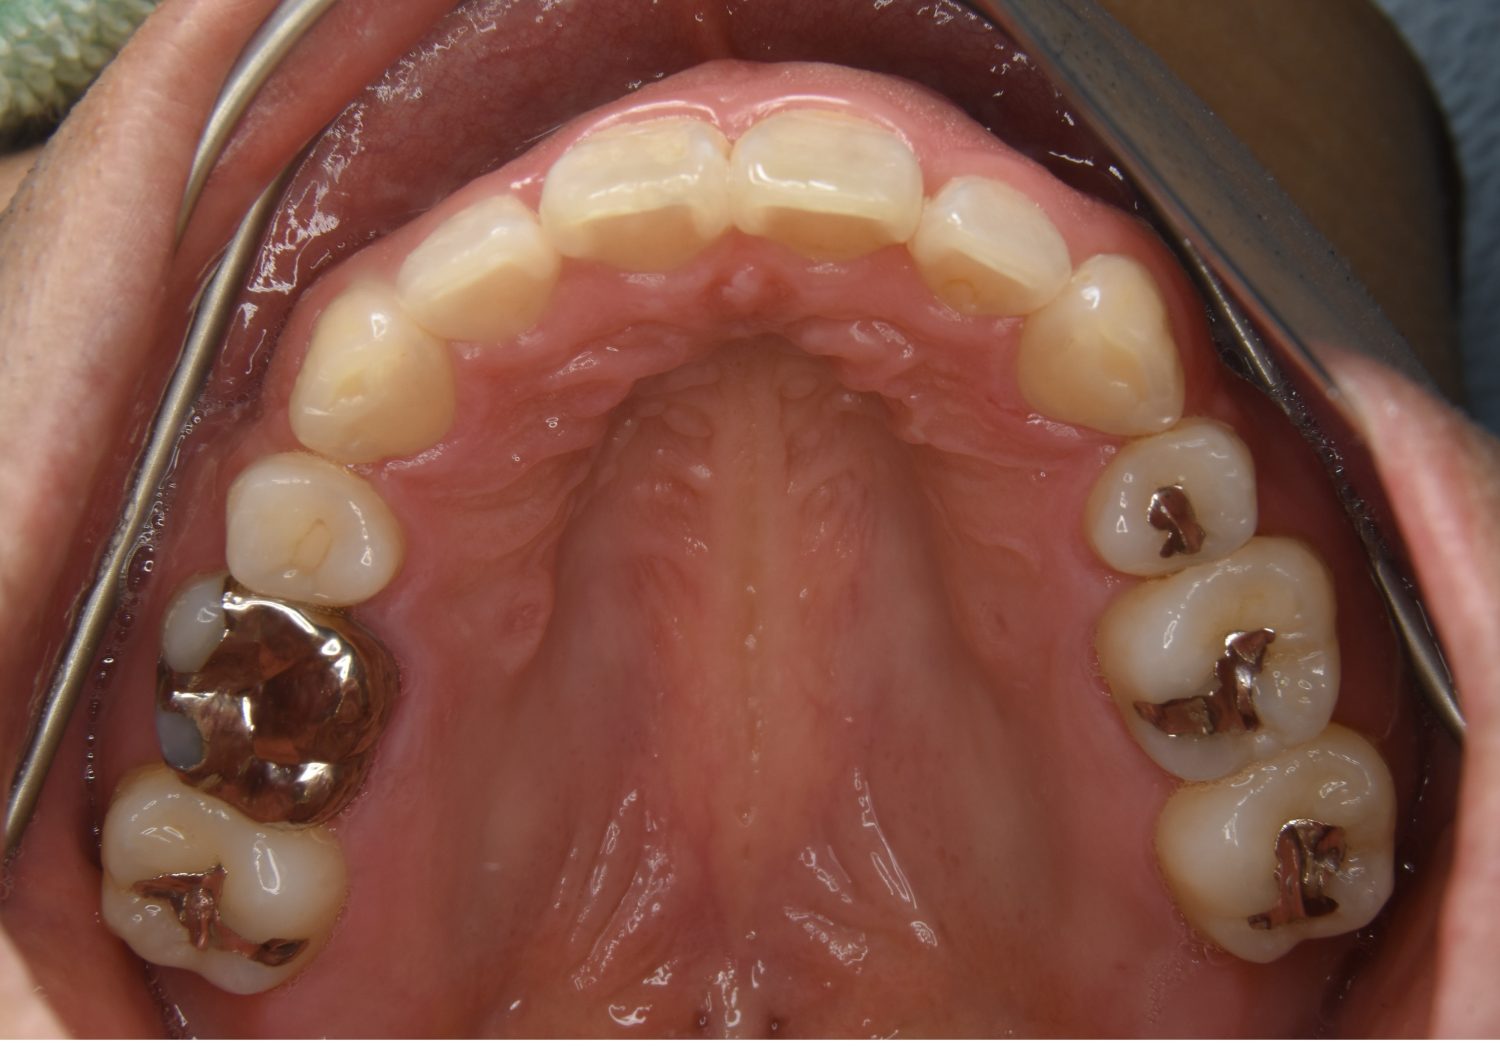

叢生の症例紹介②

Before

After

主訴

歯の凸凹を治したい。

治療内容

アライナー(インビザライン)にて非抜歯で治療を行いました。

治療費

1,150,000 円(税込)

治療期間

26ヶ月

通院回数

14回

想定されたリスク

※歯根吸収、歯肉退縮、歯髄壊死、顎関節症状

※アライナー(インビザライン)は日本の薬機法未承認の矯正装置であり、医薬品副作用被害救済制度の対象外となる場合があります。

丸山和宏先生

ピーススマイル矯正歯科

上下前歯部に叢生(凸凹)が認められる状態でした。歯列の遠心移動を行うことで機能面および審美面が改善されました。